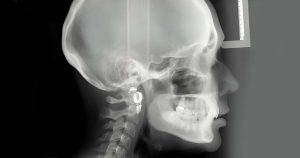

2. Cephalometric X-rays – This specific view depicts the profile of the head specifically highlighting the coordinates of dental and skeletal structures along with the soft-tissue profiles. This is mainly utilized by orthodontists for assessing the malalignment of teeth, planning their respective treatments, and verifying the post-treatment results too.